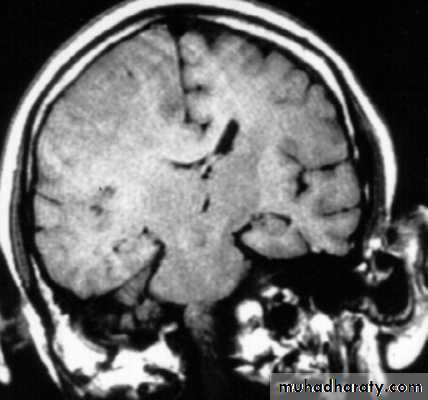

4. Diffuse brain oedema or swelling: due to encephalitis, meningitis, diffuse head injury, subarachnoid haemorrhage, Reye's syndrome, water intoxication from fluid overload.5. Idiopathic intracranial hypertension is a disease most commonly found in adult female patients (also called pseudotumour cerebri).

6. Systemic hypertension can cause breakdown of the blood brain barrier and causes hypertensive encephalopathy.